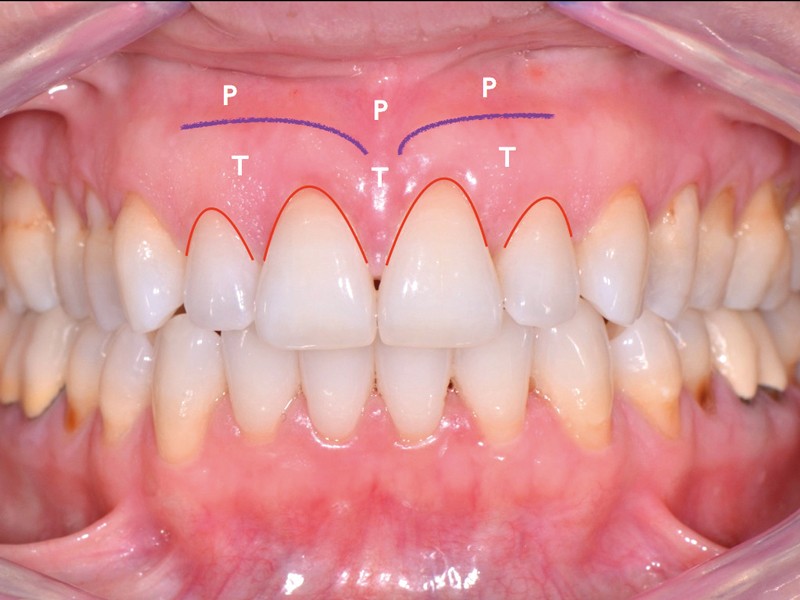

L’examen clinique révèle un biotype de type III et IV de Maynard et Wilson [1], dans les secteurs latéraux, une inflammation modérée en corrélation avec des dépôts supra-gingivaux et des restaurations débordantes, l’absence de poches parodontales, des pertes papillaires de classe I de Nordland et Tarnow [2] et des récessions gingivales associées à des lésions cervicales d’usure non carieuses et carieuses (35/45) majoritairement comblées par des restaurations en résine composite (fig. 1).

La patiente présente une parodontite chronique modérée généralisée stabilisée [4]. Étant donné la perte d’attache interproximale, les récessions sont de classe III de Miller [5] ou RT2 de Cairo [6] associées à des lésions cervicales d’usure.